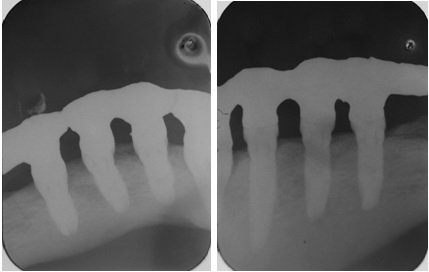

Figuras 4 e 5 – Controle radiográfico periapical após dez anos da colocação de implantes. Observar o bom contorno ósseo peri-implantar